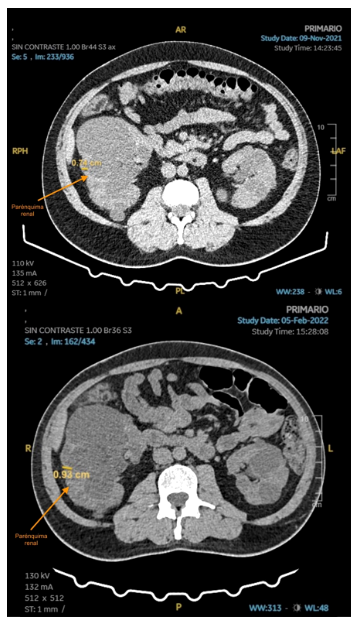

El volumen de los riñones fue medido por TC, tanto al inicio como en el control a las 12 semanas (Tabla 2) y el examen fue realizado sin contraste, las imágenes por TC tienen una precisión y coeficiente de confiabilidad similares a los de la RM 6 y son más accesibles para el paciente. Para el último control, se indicó una RM renal sin contraste. Al comparar las imágenes iniciales con el control de 12 semanas, se aprecia reducción del volumen de ambos riñones, así como el incremento del parénquima renal medido a nivel del hilio renal (Figuras 1 y 2). No se pudo contar con los formatos digitales de la RM para realizar la medición del parénquima en la semana 64.

Figura 1. UROTEM de riñón izquierdo donde se aprecia parénquima a nivel de hilio renal, basal (imagen superior) y al finalizar la semana 11 de VLCKD (imagen inferior).